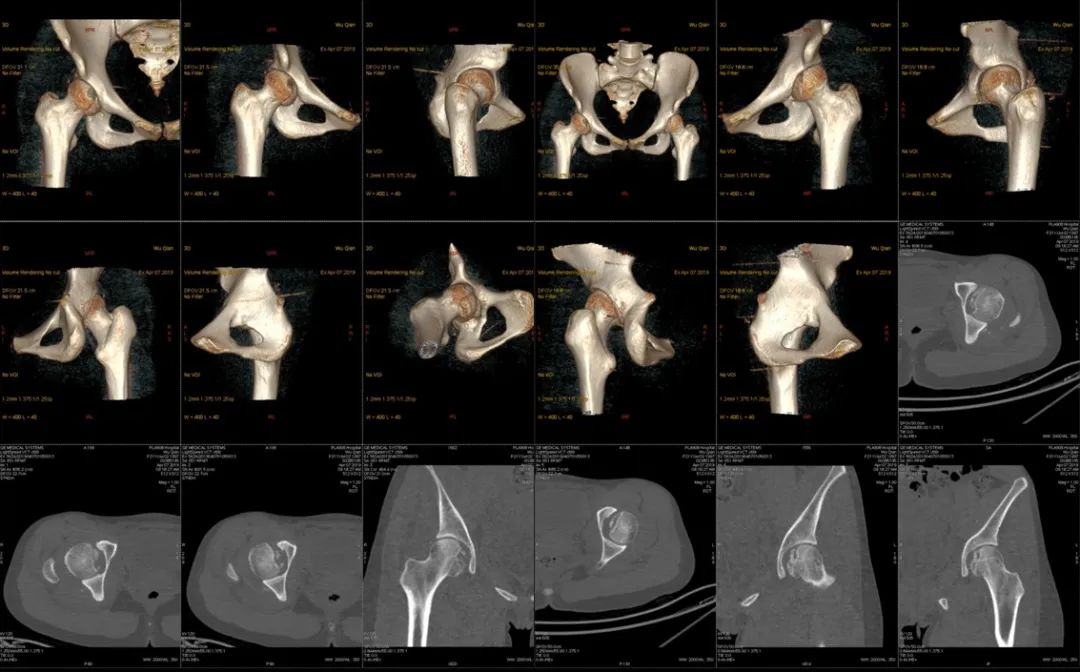

骨盆CT示:双髋关节后脱位伴双股骨头骨折。

影像学检查